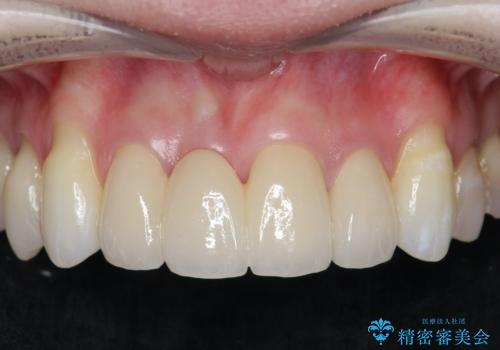

[ 再生治療・歯周外科・小矯正・セラミック補綴 ] 前歯の歯周病治療

担当医 大元洋佑